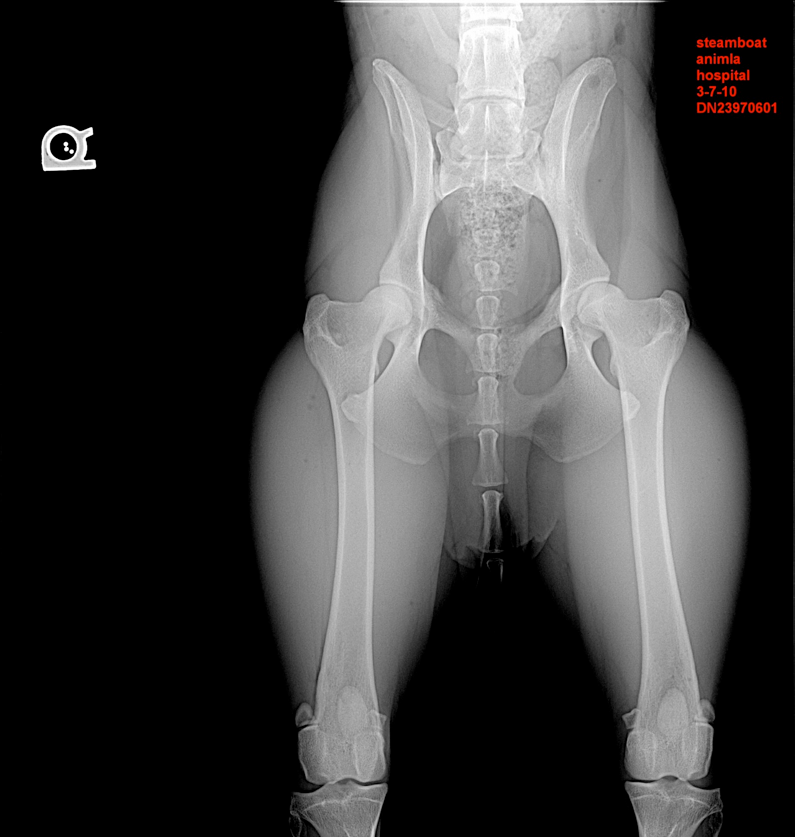

Shale hip x-ray